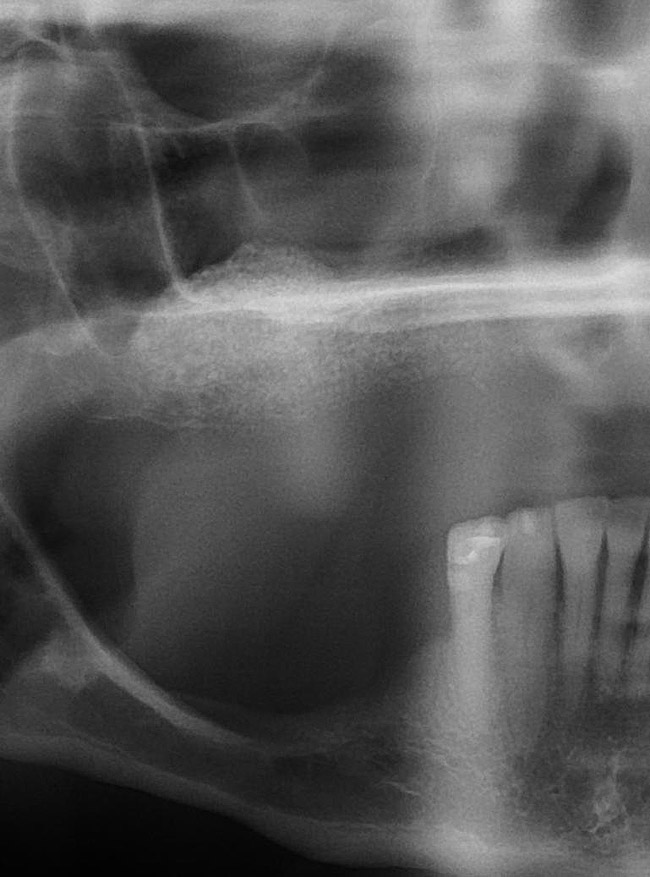

Figure 1  Buccal and radiographic views of posterior edentulism with significant sinus pneumatization in the molar region.

Figure 1

Figure 2  Buccal and radiographic views of posterior edentulism with significant sinus pneumatization in the molar region.

Figure 2